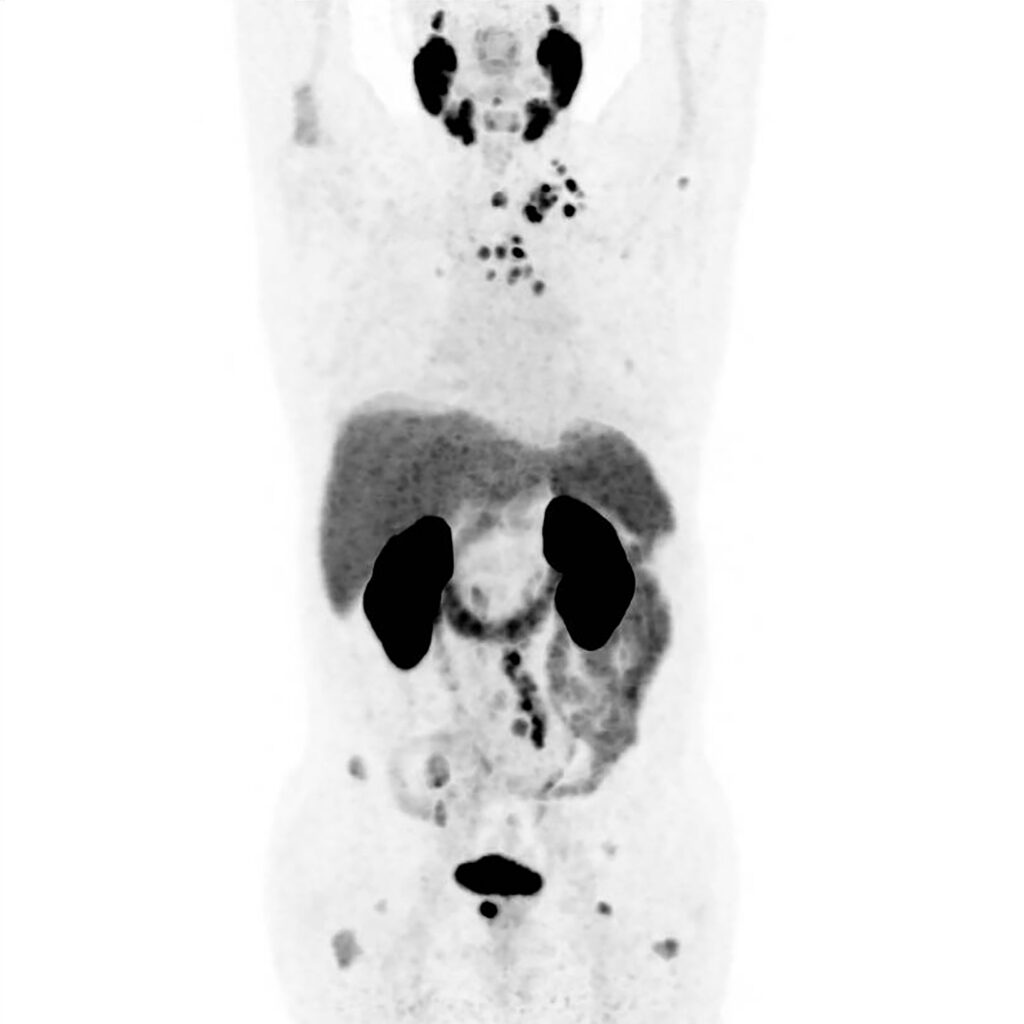

Am Freitag erwartete mich eine PET-CT-Untersuchung. Ich wollte ja schon immer mal auch von innen heraus strahlen. Ich sollte eine schwach radioaktive Flüssigkeit in die Armvene injiziert bekommen, damit sich das markierte Medikament in Geweben mit hoher Stoffwechselaktivität anreichert – wie beispielsweise in Tumoren – und so eine präzise Lokalisierung der Befunde ermöglicht.

Die PET-CT verlief problemlos und nach 30 Minuten durfte ich mich wieder ankleiden. Die Daten würden direkt an die Klinik übermittelt und die Mitarbeiterin wünschte mir aufrichtig viel Erfolg bei meiner Behandlung. Damit hatte ich die vorerst letzte Untersuchung hinter mich gebracht. Am Montag stand das Abschlussgespräch in der Klinik an. Nun hatte ich das Wochenende, um mich ein wenig von den physischen und psychischen Strapazen der letzten zwei Wochen zu erholen. Meine Tankfüllung blinkte bereits auf Reserve.

Ich wollte endlich mal Ordnung in den Papierstapel aus Befunden, Analysen und Rechnungen bringen. Der Bürokrat in mir bat um Aufmerksamkeit. Dabei fiel mir auch der Befund der PET-CT-Untersuchung in die Hände. Diesem hatte ich bis dato noch keine Aufmerksamkeit geschenkt. Mit meinem medizinischen Duolingo-Wortschatz kam ich allerdings nicht weiter und bat schwachsinnigerweise ChatGPT um Unterstützung. Hätte ich wohl besser bleiben lassen.